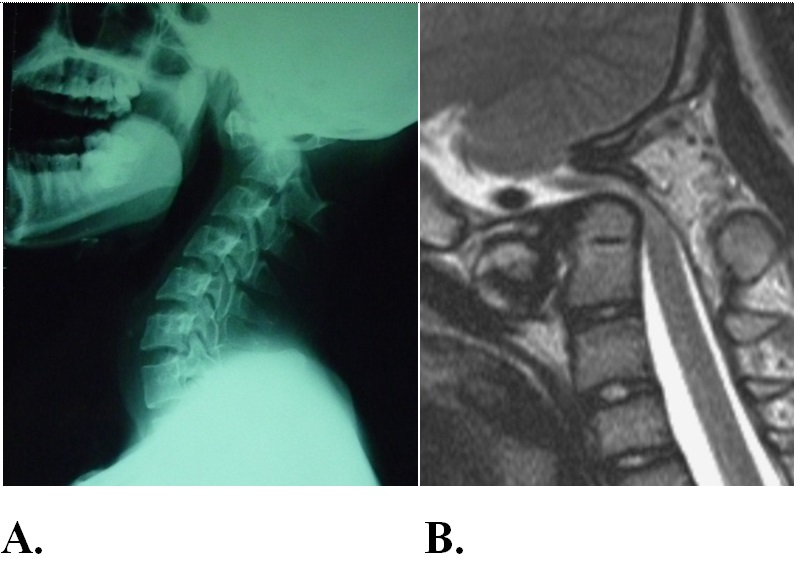

Hình 1. Hubet5555 chuẩn mã hóa SSL quốc tế nam, 33 tuổi. Năm 13 tuổi, đá bóng ngã, sau ngã liệt tứ chi, phục hồi dần. Trước khi vào viện 3 năm thấy tứ chi yếu dần. Vào viện trong tình trạng bại nặng tứ chi, tiểu qua sonde, khó thở nhẹ. Trên phim X-quang (A) có mất vững, biến dạng khớp đội - trục. Trên cộng hưởng từ (B), ống sống bị hẹp, tủy sống bị đè ép mức độ nặng.